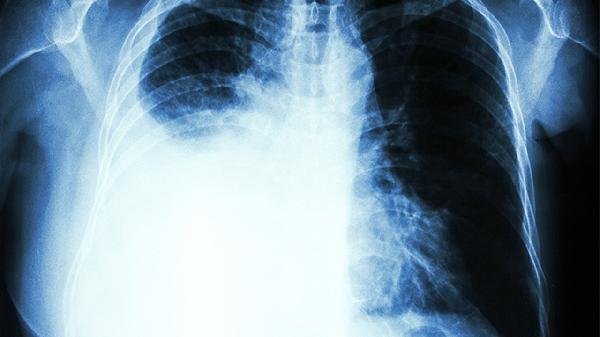

油烟中的PM2.5颗粒物能穿透呼吸道屏障,直接沉积在肺泡中。长期积累会引发慢性炎症,增加癌变风险。